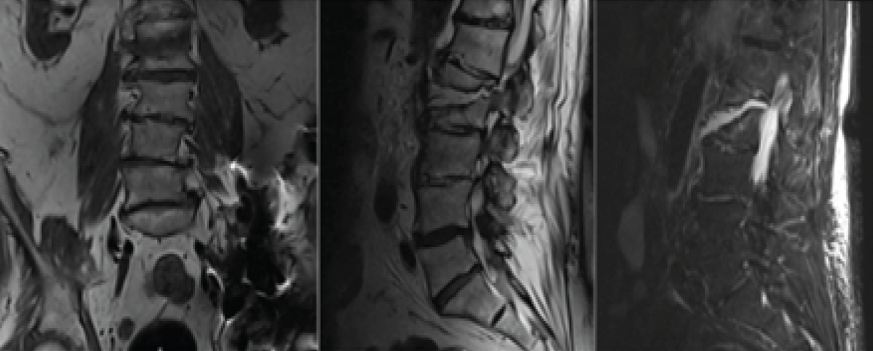

Magnetic resonance imaging on POD 5 was additionally significant for L1-L2 severe right sided neural foraminal narrowing secondary to distracted fragment of L2, at which point the patient was diagnosed with unstable L2 hyperextension fracture and neurosurgery was consulted (Fig. 4).

Figure 4: (Left) Coronal T2-weighted magnetic resonance imaging (MRI) significant for L2 hyperextension fracture. (Middle) Sagittal T2-weighted MRI significant for L2 hyperextension fracture. (Right) Sagittal short tau inversion recovery weighted MRI significant for L2 hyperextension fracture.